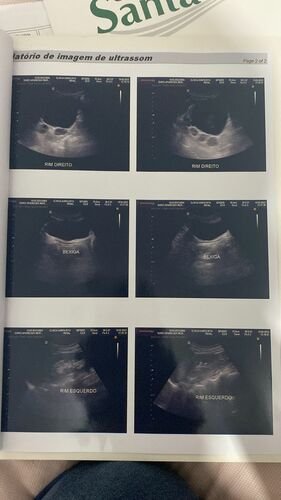

Meu nome é Bruna criei está vaquinha no intuito de ajudar minha tia Darcy que no momento não tem condições de pagar por uma tomografia que ela necessita fazer com urgência, por motivo do qual através de ultrassom e exames não conseguir descobrir o real motivo te tantas dores fortes que vem sentindo e as idas de várias vezes ao pronto socorro por dor. E pelo SUS não faz a tomografia que ela necessita como podem ver no exames o médico pede com urgência…. Agradeço desde já que Deus abençoe a todos que contribuírem..